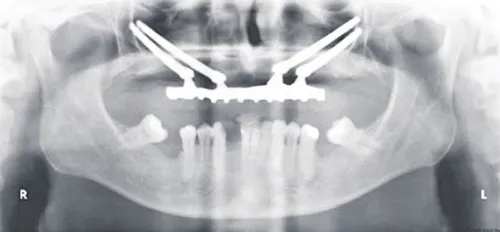

Yukarıda röntgeni görülen hasta, üst çene arka bölgede yeterli kemik olmaması nedeniyle kemik greftleri ve sinus yükseltme operasyonları için adaydır fakat zigoma implantlarının kullanımı sayesinde bu cerrahi prosedürlere gerek kalmamıştır. Zigomatik implant cerrahisi en iyi, derin sedasyon veya genel anestezi altında gerçekleştirilir.